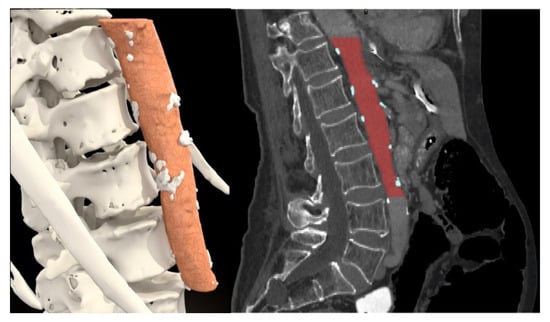

| Median psoas muscle area/height (IQR) (cm2/m) | 7.16 (5.01–9.41) | 7.61 (5.38–9.70) | 5.19 (4.06–7.39) | <0.001 |

| Number of patients with psoas area/height under cut-off point | 94 (36.0%) | 65 (30.2%) | 29 (63.0%) | <0.001 |

| Median osteopenia in ROI at L3 (IQR) (HU) | 138.1 (102.1–181.0) | 144.0 (109.6–193.8) | 100.6 (74.6–142.5) | <0.001 |

| Number of patients with osteopenia under cut-off point | 61 (23.4%) | 38 (17.7%) | 23 (50.0%) | <0.001 |